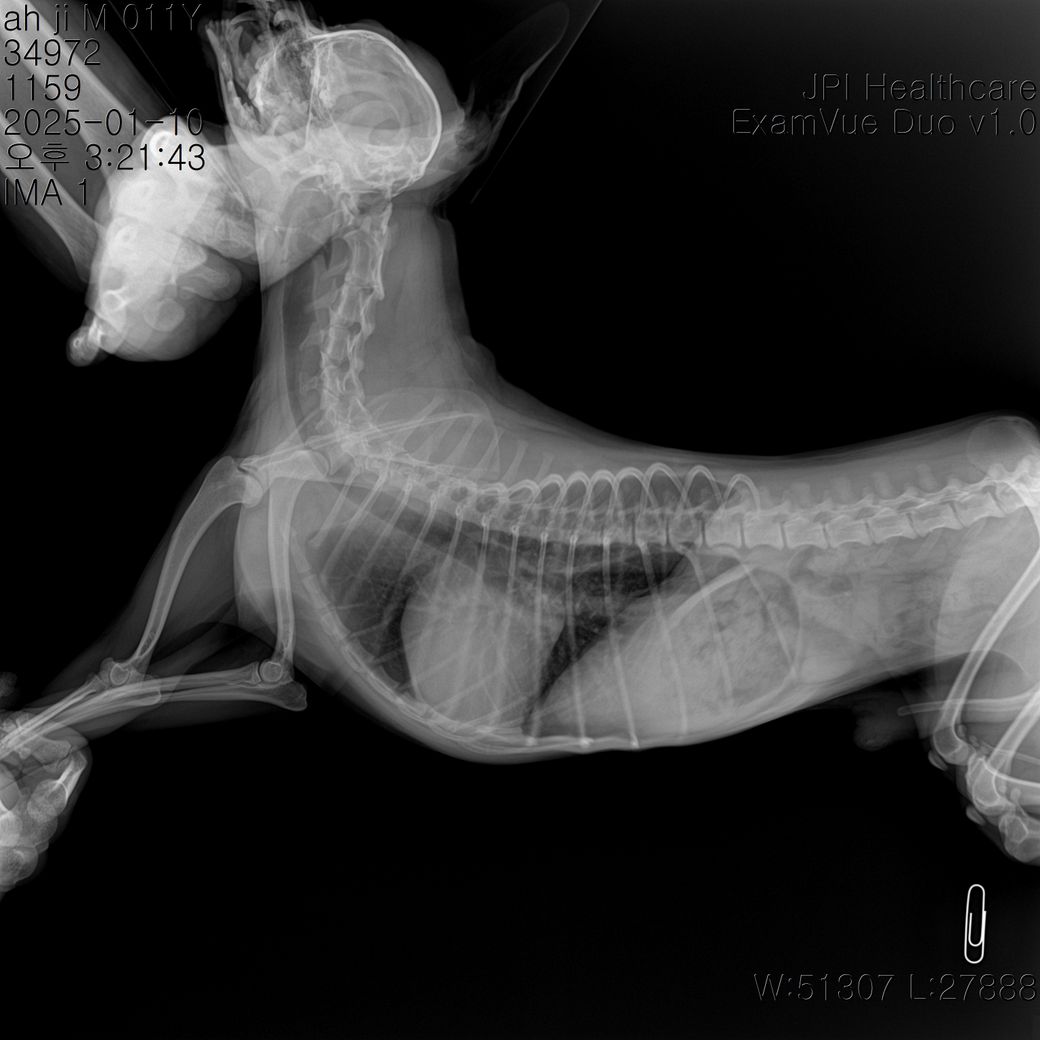

안녕하세요 심장관련 방사선 사진 봐주실 수 있나요?

안녕하세요 며칠전 방사선 촬영을 했는데요

혹시 심장비대가 관찰되는지 궁금합니다

외측상에서 심장의 크기가 늑간기준으로 4.5개로 평가되어 심한 심비대 양상이 관찰되며, 심장의 뒤쪽 허리 소실 소견과 복배상 심장의 2~3시 사이 돌출 양상, 심장의 뒤쪽 변연이 2중으로 관찰되는 양상 등 심한 좌심방 종대 양상이 관찰됩니다. 복배상 폐 후엽을 중심으로 경미한 폐 침윤 양상이 관찰되어 폐수종이 진행되고 있는것으로 보이는 바 즉각적인 처치를 하지 않을 경우 응급상황 발생 가능성이 높은 상태로 보입니다. 주치의와 상의하에 공격적인 치료 처치가 권장되는 전형적인 심장 질환 환자의 방사선 사진입니다.